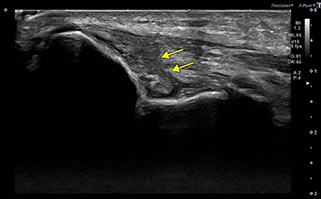

岩本部長は、肘関節の軟骨について、Aplio i800のSmart FusionでMR画像をリファレンスとした観察を数例行った。「MR画像とのフュージョンで、超音波画像で軟骨の状態がどれだけ評価できるかを検証するために行いました。実際の手術の際の解剖と比較しても、超音波画像の描出能は高いと思います。Smart FusionではMR画像を参照して同部位を描出することが可能です」。また、iSMIについても、「iSMIでは低速で微細な血流が描出可能で、腱の付着部などの症状が判断できるのではと期待しています」と述べる。

図2 肘内側側副靭帯(UCL)損傷 |